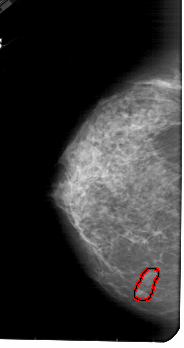

A_1842_1.RIGHT_CC

RIGHT_MLO LINES 5491 PIXELS_PER_LINE 2821 BITS_PER_PIXEL 12 RESOLUTION 43.5 NON_OVERLAY

FILE: A_1842_1.LEFT_CC.OVERLAY

TOTAL_ABNORMALITIES 1

ABNORMALITY 1

LESION_TYPE MASS SHAPE LOBULATED MARGINS CIRCUMSCRIBED

ASSESSMENT 4

SUBTLETY 3

PATHOLOGY BENIGN

TOTAL_OUTLINES 1

BOUNDARY